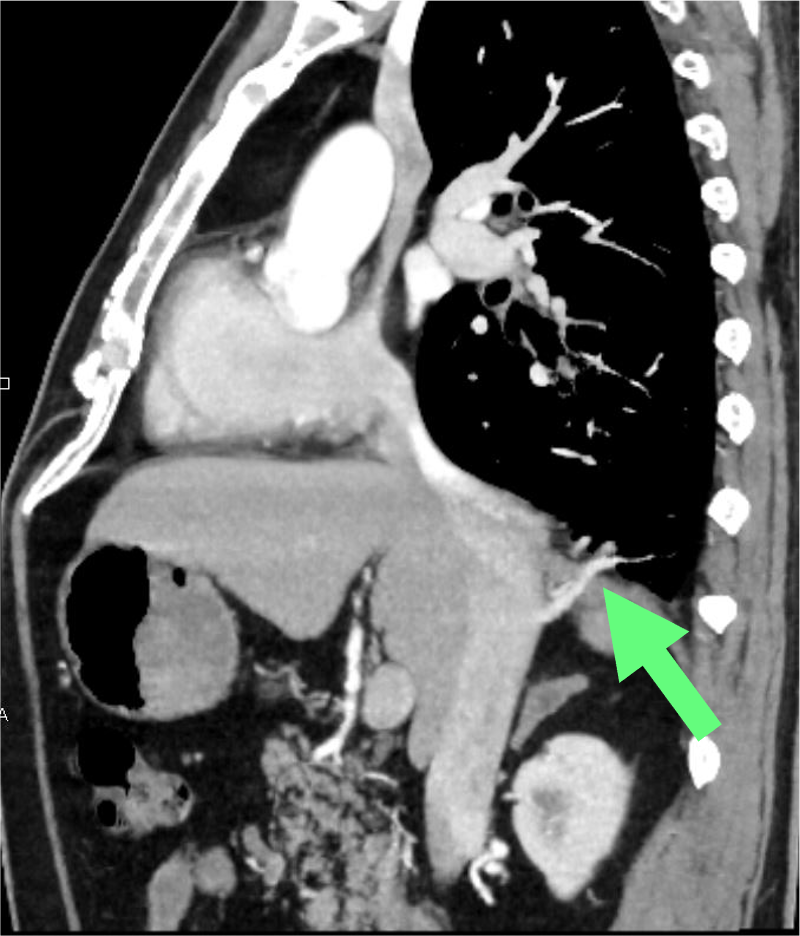

図5.造影CT(動脈相)矢状断MIP像

図4で示した肺静脈の造影CT(動脈相)partial MIP矢状断像。右肺底部から還流を受ける肺静脈は、図1-3に示した静脈よりも下方で肝部下大静脈に流入している(矢印)